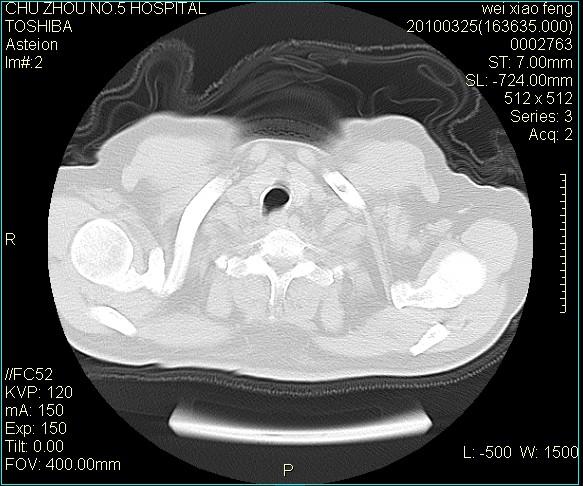

男,60岁,反复咳、痰、喘3月,加重3天。

双肺间质性改变。

间质性肺炎伴间质纤维化!不排除伴有职业病!

考虑尘肺

右肺中叶结节影为原发灶,考虑右肺中叶周围型肺癌并淋巴道转移